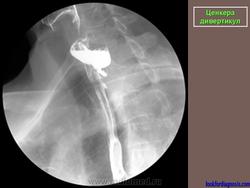

Ценкера дивертикул.

Barium swallow with fluoroscopy, lateral view</p> <p>During swallowing an outpouching of the posterior hypopharyngeal wall is clearly visualised at the level C5-C6, right above the upper oesophageal sphincter. The pouch is characterized by a narrow neck entrapping some barium after the swallowing.

Zenker's diverticulum AP </p> <p>

ID: 13718 Zenkers diverticulum Dr Lee-Anne Slater - 10 May 2011 Barium swallow showed a large posterolateral pouch just above the level ...